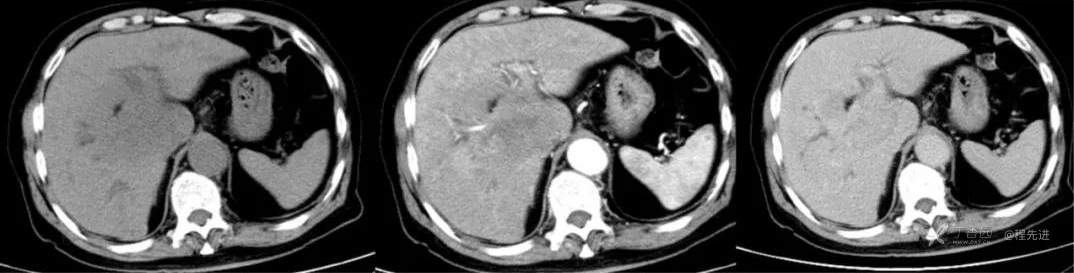

红五月特别精彩病例|胸部不适CT检查发现肝门区占位【病理已公布】

简要病史:因胸部不适入院,胸部CT示:肺部感染性病变;腹部CT示:肝门区占位性病变

既往史:有乙型肝炎病毒感染病史,未接受系统治疗

辅助检查:白细胞12.33×10^9/L 谷丙转氨酶 70u/L 谷草转氨酶90u/L